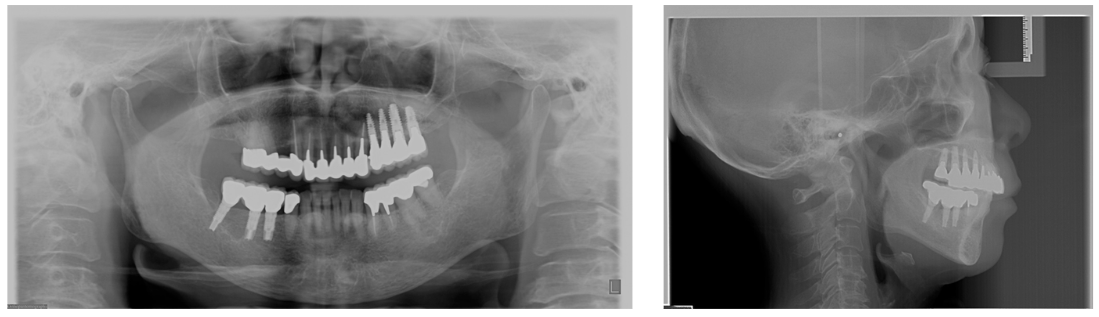

多数歯欠損のインプラント治療の症例(うえだ歯科)

| 主訴 | 歯がグラグラで噛むことができない。インプラントをして欲しい。 |

| 治療内容 | 歯周病で骨の吸収が重度で保存不能なため抜歯、仮の入れ歯を作り、6ヶ月の抜歯窩の治療の後に、インプラントのCTによる診査診断を行い、下顎に6本インプラント埋入と同時に仮歯を入れる。その後、上顎は8本のインプラント埋入と同時に仮歯を入れる。左右上6はソケットリフトによる上顎洞拳上術を行う。その後免荷期間6ヶ月待ってセラミックを用いた上部構造作製、装着しメンテナンスに移行する。 |

| 治療費 | 9,000,000円(税込) |

| 治療期間 | 2年3ヶ月 |

| 治療回数 | 90回 |

| 想定されたリスク | 重度の歯周病により無歯顎になったため、プラークコントロール不良による、術後のインプラント周囲炎が懸念される。歯冠の部分はセラミックなため欠ける可能性がある。 |